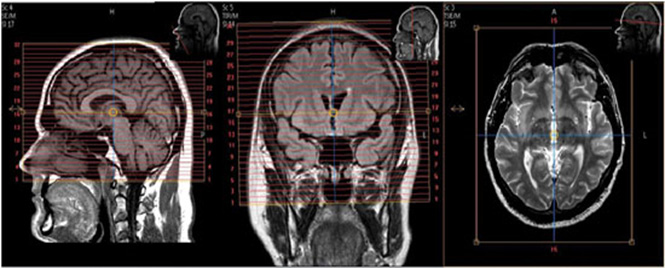

Following parameters remain consistent:1. Plane – sagittal

2. Mode – 3D

3. T1 weighted - Always

4. Matrix – 192 x 192

5. NEX / NSA – 1

6. Slice thickness – 1.2 mm

7. Spacing – 1.2 mm

8. Number of slices – 160 - 170

9. FOV 24 – 25.6NOTE: Some NeuroQuant parameters vary depending on scanner manufacturer & field strength

| SAG | T1 | 3D TFE | 1.2 (160-170 slices) | 0 | no | 24-25.6 | no | Send to NQ_MS. See specific NeuroQuant 3D T1 scan parameters above. |